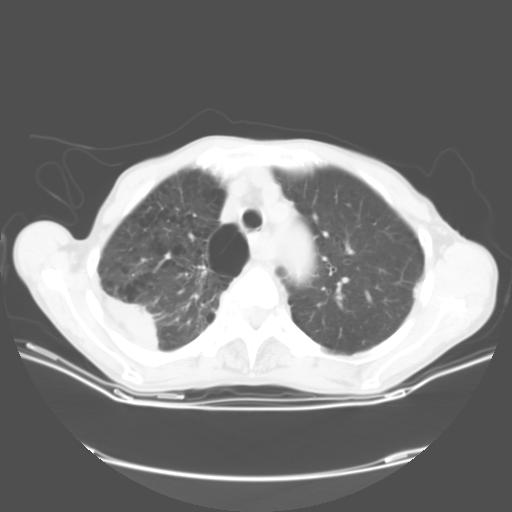

女,72岁,咳嗽一周余,突发右下肢无力二天。

来院做头颅+胸部ct平扫

胸部病变平扫35hu,增强强化至70hu

这个病人首先是胸部病变的定位到底是肺内还是肺外。仔细观察块影位于胸膜下,与胸膜间有透亮带,且近端血管未见明显推移而是引流样改变,形态分叶,说明这个病灶位于肺内胸膜下。很可能是腺癌,腺癌最易致颅内高密度转移灶。局部胸膜有侵犯。

本例颅内见多发大小不等高密度灶,有强化及水肿;另外,胸锁关节层面可能是第四胸椎及右侧肋骨起始部骨质欠连续,椎旁软组织肿胀,建议调骨窗观察。

诊断:右下肺癌伴颅内、胸椎、肋骨转移可能性最大。